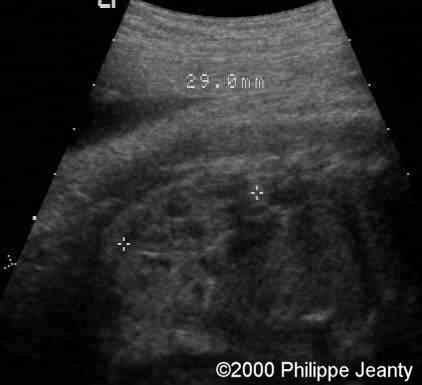

The other is 29 mm. So both kidneys are just a little above half the normal size ! Surprisingly this was not recognized by many.

case0020-6b